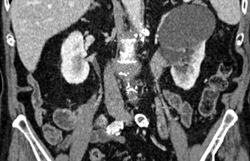

Prehilar Branching of Right Renal Artery and Ras